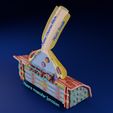

神经肌肉接头示意图